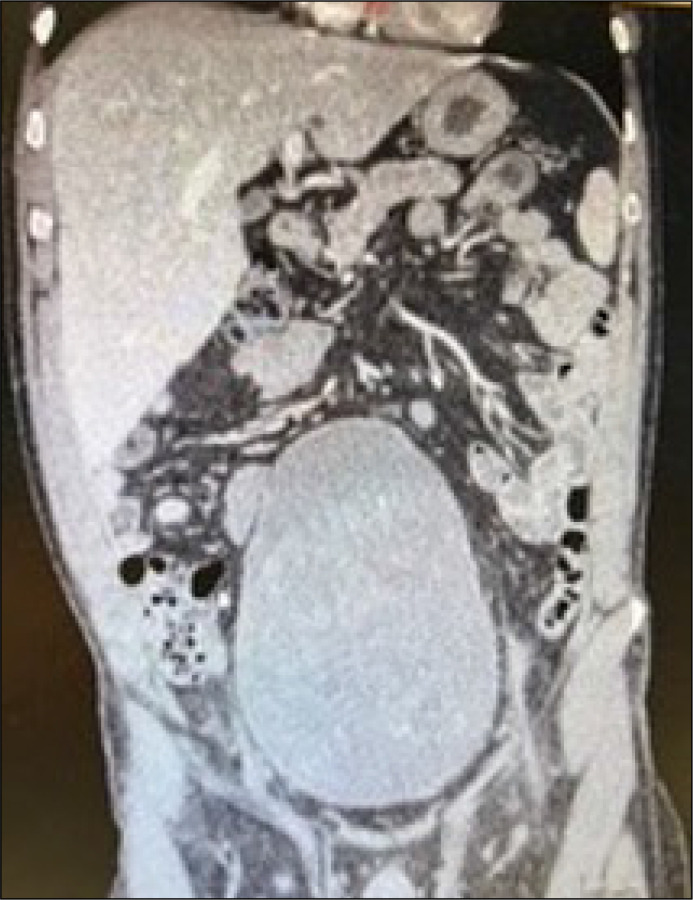

摘要膀胱平滑肌肉瘤是一种极为罕见的泌尿生殖系统恶性肿瘤。我们报告一位59岁的白种人男性患巨大膀胱平滑肌肉瘤的病例。患者接受手术切除膀胱-腹腔镜根治性膀胱切除术并扩大盆腔淋巴结切除术,并通过双侧输尿管皮瘘转移尿。从宏观和微观上看,切除是完全的。没有额外的辅助治疗。在6个月的随访中,患者放射学缓解。手术切除并扩大盆腔淋巴结切除术似乎足以治疗膀胱平滑肌肉瘤。

Urinary bladder leiomyosarcoma is an extremely rare malignancy of the urogenital system. We present the case of a 59-year-old Caucasian male with a gigantic bladder leiomyosarcoma. The patient was subdued to the surgical excision of the urinary bladder - laparoscopic radical cystectomy with extended pelvic lymphadenectomy, with urinary diversion by bilateral ureterocutaneostomy. The excision was complete both macroscopically and microscopically. No additional adjuvant therapy was administered. In the 6-month follow-up, the patient remained in radiological remission. Surgical excision with extended pelvic lymphadenectomy seems to be sufficient in the treatment of urinary bladder leiomyosarcoma.